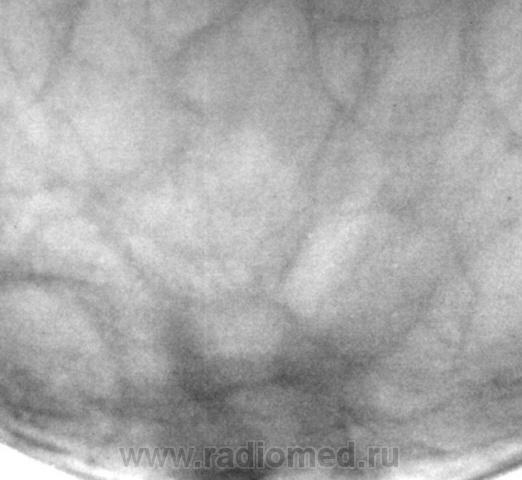

"Уплотнение" пропальпировано хирургом в передних отделах молочной железы...

На представленных снимках патологии нет, но учитывая наличие пальпируемого уплотнения нельзя исключить липому.

а практически по центру на всех маммограммах: разве не мелкий узел с тяжистым контуром, примерным размером 1.5-2 см (масштаб не ясен). такие вещи в ГО: аденокарцинома